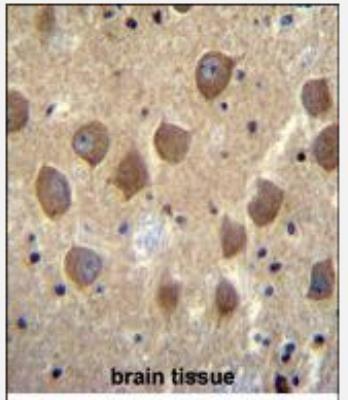

Supportive validation

- Submitted by

- Novus Biologicals (provider)

- Main image

- Experimental details

- Immunohistochemistry-Paraffin: Protocadherin beta 3 Antibody [NBP2-30035] - Immunohistochemistry analysis in formalin fixed and paraffin embedded human brain tissue followed by peroxidase conjugation of the secondary antibody and DAB staining.This data demonstrates the use of PCDHB3 Antibody (N-term) for immunohistochemistry. Clinical relevance has not been evaluated.